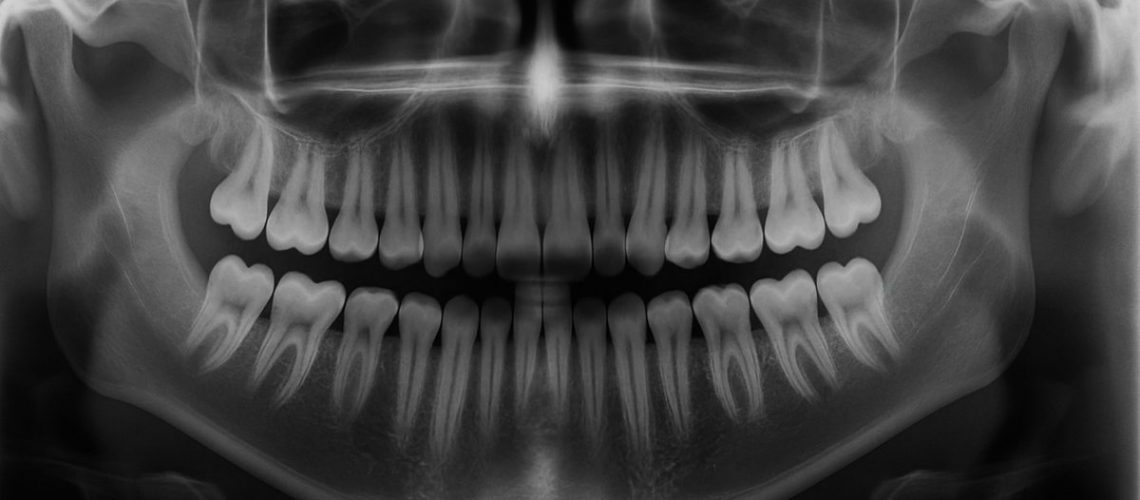

An x-ray image of an adult mouth, clearly showing 28 teeth present and empty spaces where wisdom teeth would typically be located. No text on the image.

Many people ask, "how many teeth do we have without wisdom teeth in Greensburg?" The short, simple answer is useful: most adults have 28 teeth if their wisdom teeth are removed or never come in. Below you’ll find a clear count, common differences, why numbers vary, and when to see a specialist about wisdom teeth or replacing missing teeth.

Most adults have 28 permanent teeth when wisdom teeth (third molars) are absent. That number can change because of genetics, extra teeth, or teeth removed for health or orthodontic reasons. If you’re asking how many teeth do we have without wisdom teeth in Greensburg, expect 28 as the typical count but know individual cases differ.

Adults normally have: 8 incisors (4 top, 4 bottom), 4 canines, 8 premolars, and 8 molars—totaling 28 without wisdom teeth. Add four wisdom teeth (one in each corner) and the total becomes 32. Each tooth type has a specific role: incisors cut, canines tear, premolars crush, and molars grind.